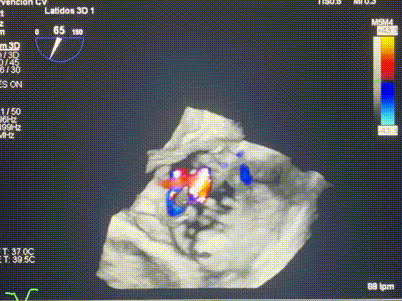

術(shù)中輸送器在超聲引導(dǎo)下調(diào)整位置

手術(shù)在全麻狀態(tài)下進(jìn)行。術(shù)者采用經(jīng)右側(cè)頸靜脈入路的方式將輸送器送入患者心臟內(nèi),在TEE及DSA引導(dǎo)下調(diào)整輸送器頭端角度,使得輸送器與三尖瓣瓣環(huán)平面垂直。在輸送器進(jìn)入右心室后釋放室間隔錨定裝置,而后釋放瓣葉夾持件(2個(gè)耳片結(jié)構(gòu))成垂直狀態(tài)。在TEE及DSA確定夾持件固定至三尖瓣葉根部且位于右室側(cè)后釋放人工瓣心房側(cè)盤片。隨后調(diào)整瓣膜同軸性以及室間隔錨定件位置(貼合室間隔),前推藏針管并固定,進(jìn)而釋放室間隔錨定裝置,并再次確認(rèn)瓣膜位置、穩(wěn)定性及同軸性,合攏輸送鞘后撤出輸送器,完成LuX-Valve Plus人工三尖瓣瓣膜的植入,僅殘余微量瓣周漏。且經(jīng)手術(shù)中心電生理團(tuán)隊(duì)評(píng)估,病人的起搏器和ICD功能沒有受到影響。